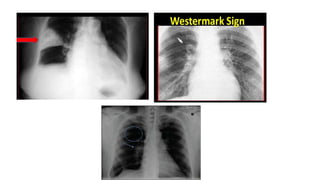

Chest X ray

• Most patients with pulmonary embolism have abnormal but nonspecific

chest radiographic findings.

• Common radiographic findings include atelectasis, pleural effusion,

pulmonary infiltrates, and mild elevation of a hemidiaphragm.

• Classic findings of pulmonary infarction—such as Hampton’s hump or

decreased vascularity (Westermark’s sign)—are suggestive but infrequent.

• Hampton hump refers to a dome-shaped, pleurally-based opacification in

the lung.

• Pala sign is a prominent pulmonary artery that can be caused either

by pulmonary hypertension that develops or by distension of the vessel by

a large pulmonary embolus.

• Westermark’s sign – peripheral oligemia.

• A normal chest radiograph in a patient with otherwise unexplained acute

dyspnea or hypoxemia is strongly suggestive of embolism.

Chest X ray •Most patients with pulmonary embolism have abnormal but nonspecific chest radiographic findings. • Common radiographic findings include atelectasis, pleural effusion, pulmonary infiltrates, and mild elevation of a hemidiaphragm. • Classic findings of pulmonary infarction—such as Hampton’s hump or decreased vascularity (Westermark’s sign)—are suggestive but infrequent. • Hampton hump refers to a dome-shaped, pleurally-based opacification in the lung. • Pala sign is a prominent pulmonary artery that can be caused either by pulmonary hypertension that develops or by distension of the vessel by a large pulmonary embolus. • Westermark’s sign – peripheral oligemia. • A normal chest radiograph in a patient with otherwise unexplained acute dyspnea or hypoxemia is strongly suggestive of embolism.